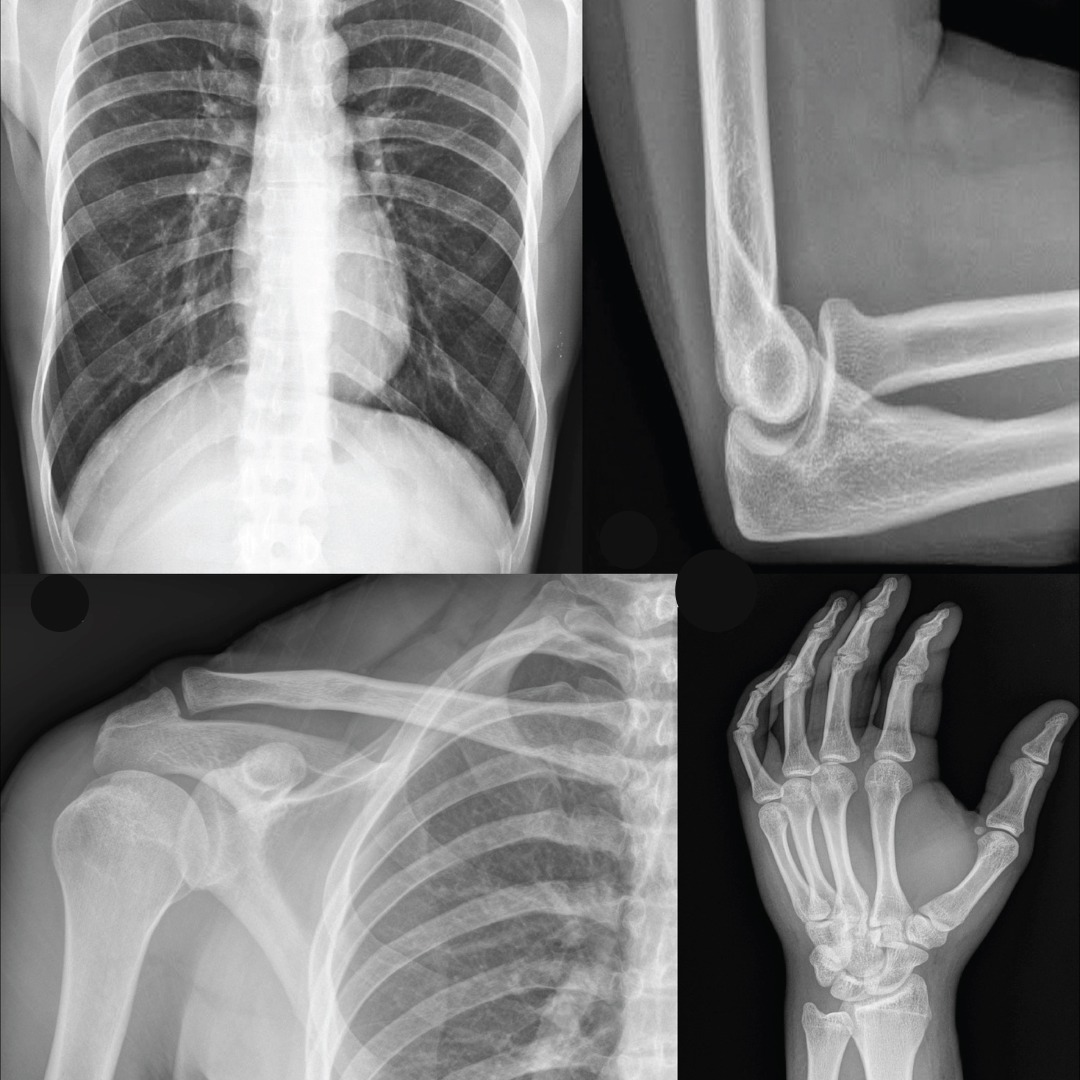

Le module radiologie d’e-Dr TIM centralise prescription, planification, réalisation et interprétation des examens (radio, scanner, IRM, échographie). Intégré aux systèmes PACS/RIS et doté d’une visionneuse DICOM, il garantit archivage sécurisé, partage fluide des résultats et accès patient. Il optimise le travail médical, accélère les diagnostics et améliore la qualité des soins.

Le module radiologie gère la planification, réalisation et interprétation des examens. Les images sont importées via PACS, visualisées en DICOM, puis analysées par le radiologue. Un compte-rendu est rédigé dans e-Dr TIM et partagé avec le médecin prescripteur et le patient. Le processus est fluide, sécurisé et intégré aux systèmes PACS/RIS.

Le module radiologie utilise une visionneuse DICOM pour afficher les images médicales en haute qualité. Il est intégré au PACS pour stocker et partager les images en toute sécurité, et au RIS pour gérer l’administration des examens. Cette technologie assure une prise en charge rapide, fiable et complète des examens radiologiques.